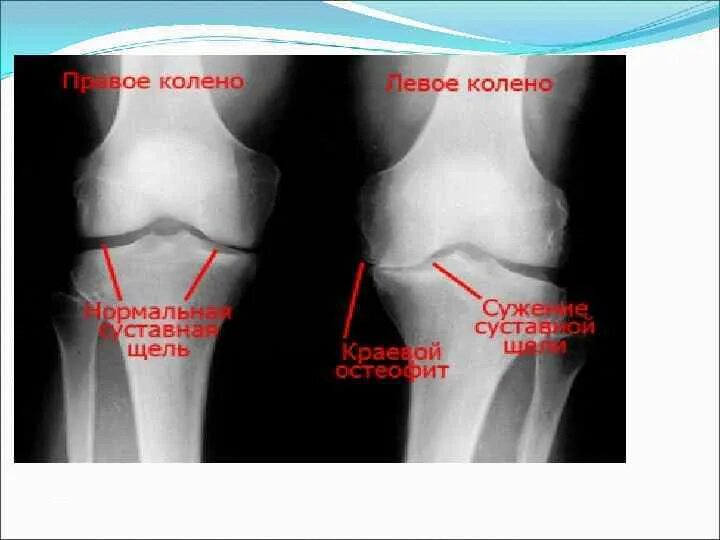

Артроз 2 степени симптомы